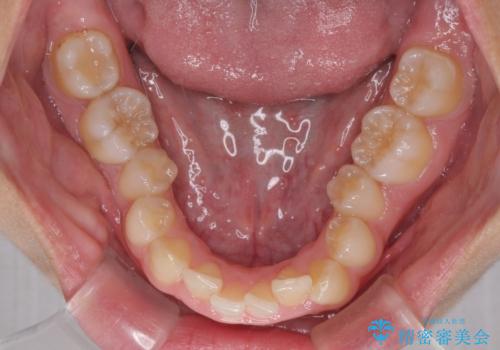

- 前歯の歯並びと不自然な色をした前歯のクラウンを気にして来院された患者様です。

上下前歯の歯列不正はインビザラインにより歯列を整え、その後に、前歯をオーダーメイドタイプのオールセラミッククラウンにて補綴治療することとしました。

前歯のデコボコを一番気にしていらっしゃいましたが、矯正治療により下顎前歯が隠れるほどのディープバイトも一緒に改善され、奥歯に負担のかかりにくい咬み合わせとなりました。